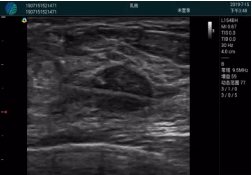

腺體內(nèi)部清晰顯示一低回聲塊影,形態(tài)不規(guī)則,邊界模糊,邊緣呈毛刺狀,內(nèi)部見砂礫樣鈣化

M20引導(dǎo)下穿刺活檢術(shù)

M20引導(dǎo)下平面內(nèi)穿刺取出的腫塊組織

M20查看:囊內(nèi)回聲均勻,邊界清晰,囊壁光滑

M20引導(dǎo)抽吸術(shù)后囊腫消失,原區(qū)域空腔形成,脂肪層與腺體層架構(gòu)發(fā)生改變

超聲以操作簡單、定位準(zhǔn)確、實(shí)時(shí)顯像、費(fèi)用低廉等優(yōu)勢,而成為麥默通乳腺活檢治療乳腺腫塊最常見的引導(dǎo)手段,已逐步在各大醫(yī)院開展此類手術(shù)。

2、超聲的可視化操作,能準(zhǔn)確的顯示病灶的位置、最大徑,選擇合適的刀具,決定切口的位置和方向,避開血管、減少出血危險(xiǎn)并實(shí)時(shí)觀察乳腺病灶的切割情況,避免造成腫塊組織殘留